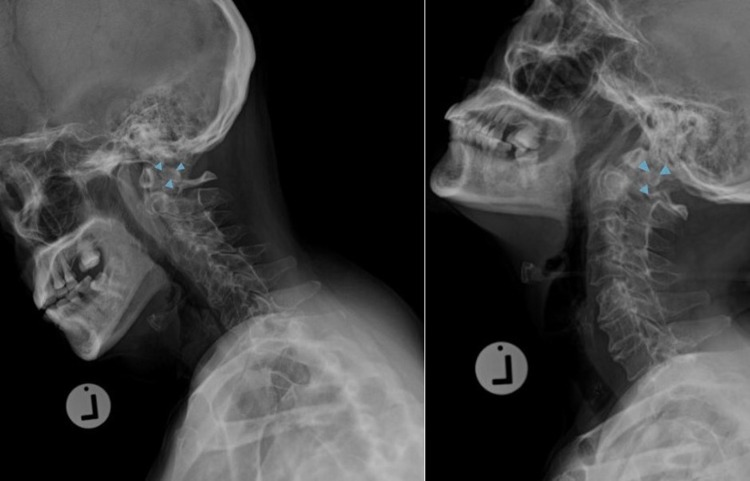

Fig. 2.

Dynamic flexion-extension radiographs of the cervical spine showed a partial reduction of C1 during flexion position (flexion view on the left panel, extension view on the right panel. Arrows in both panels showed os odontoideum)